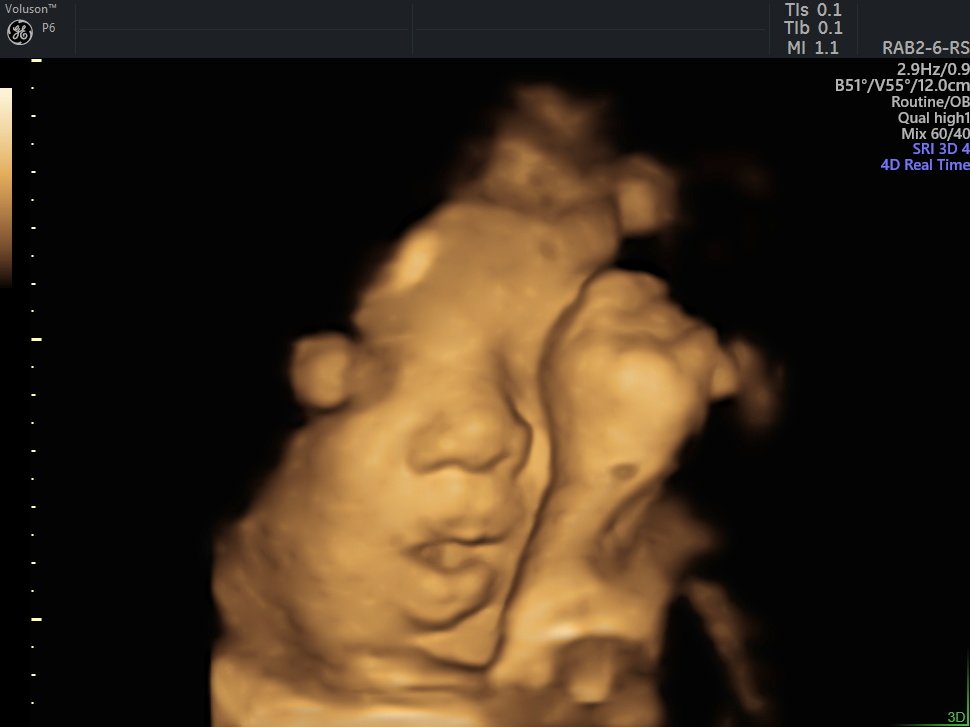

4 D Ultrasonografi

4 Boyutlu (Renkli) Ultrason ve Doppler Ultrasonografi